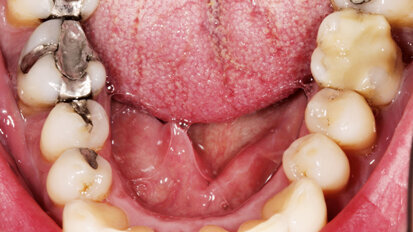

Rehabilitace Straumann